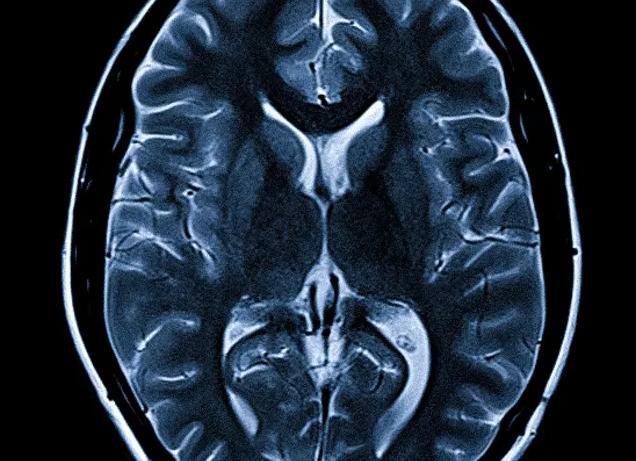

МРТ гипофиза при повышенном пролактине является наиболее информативным методом обследования.

Методика обследования головного мозга подразумевает изучение функционирования гипофиза. Для этого в организм пациента вводится специальное контрастное вещество.

Сканирование позволяет выявить формирование следующих образований на начальных этапах их развития:

- наличие аденомы и ее локализацию;

- опухоли, находящиеся в мягкотканных формированиях;

- позволяет выявить наличие образований в кавернозном синусе.

Компьютерная томография головного мозга – не менее информативный метод, позволяющий визуализировать костные структуры. Эта методика позволяет просмотреть область нахождения гипофиза.

- МРТ головного мозга;

- компьютерную томографию;

МРТ гипофиза при повышенном пролактине обладает высокой степенью специфичности, достоверности. Позволяет выявить микроаденомы, верифицировать размеры, контуры, детали структуры. Когда исследование обнаруживает доброкачественную опухоль, проводят динамический контроль передней черепной ямки через 6 месяцев на предмет увеличения размеров образования.